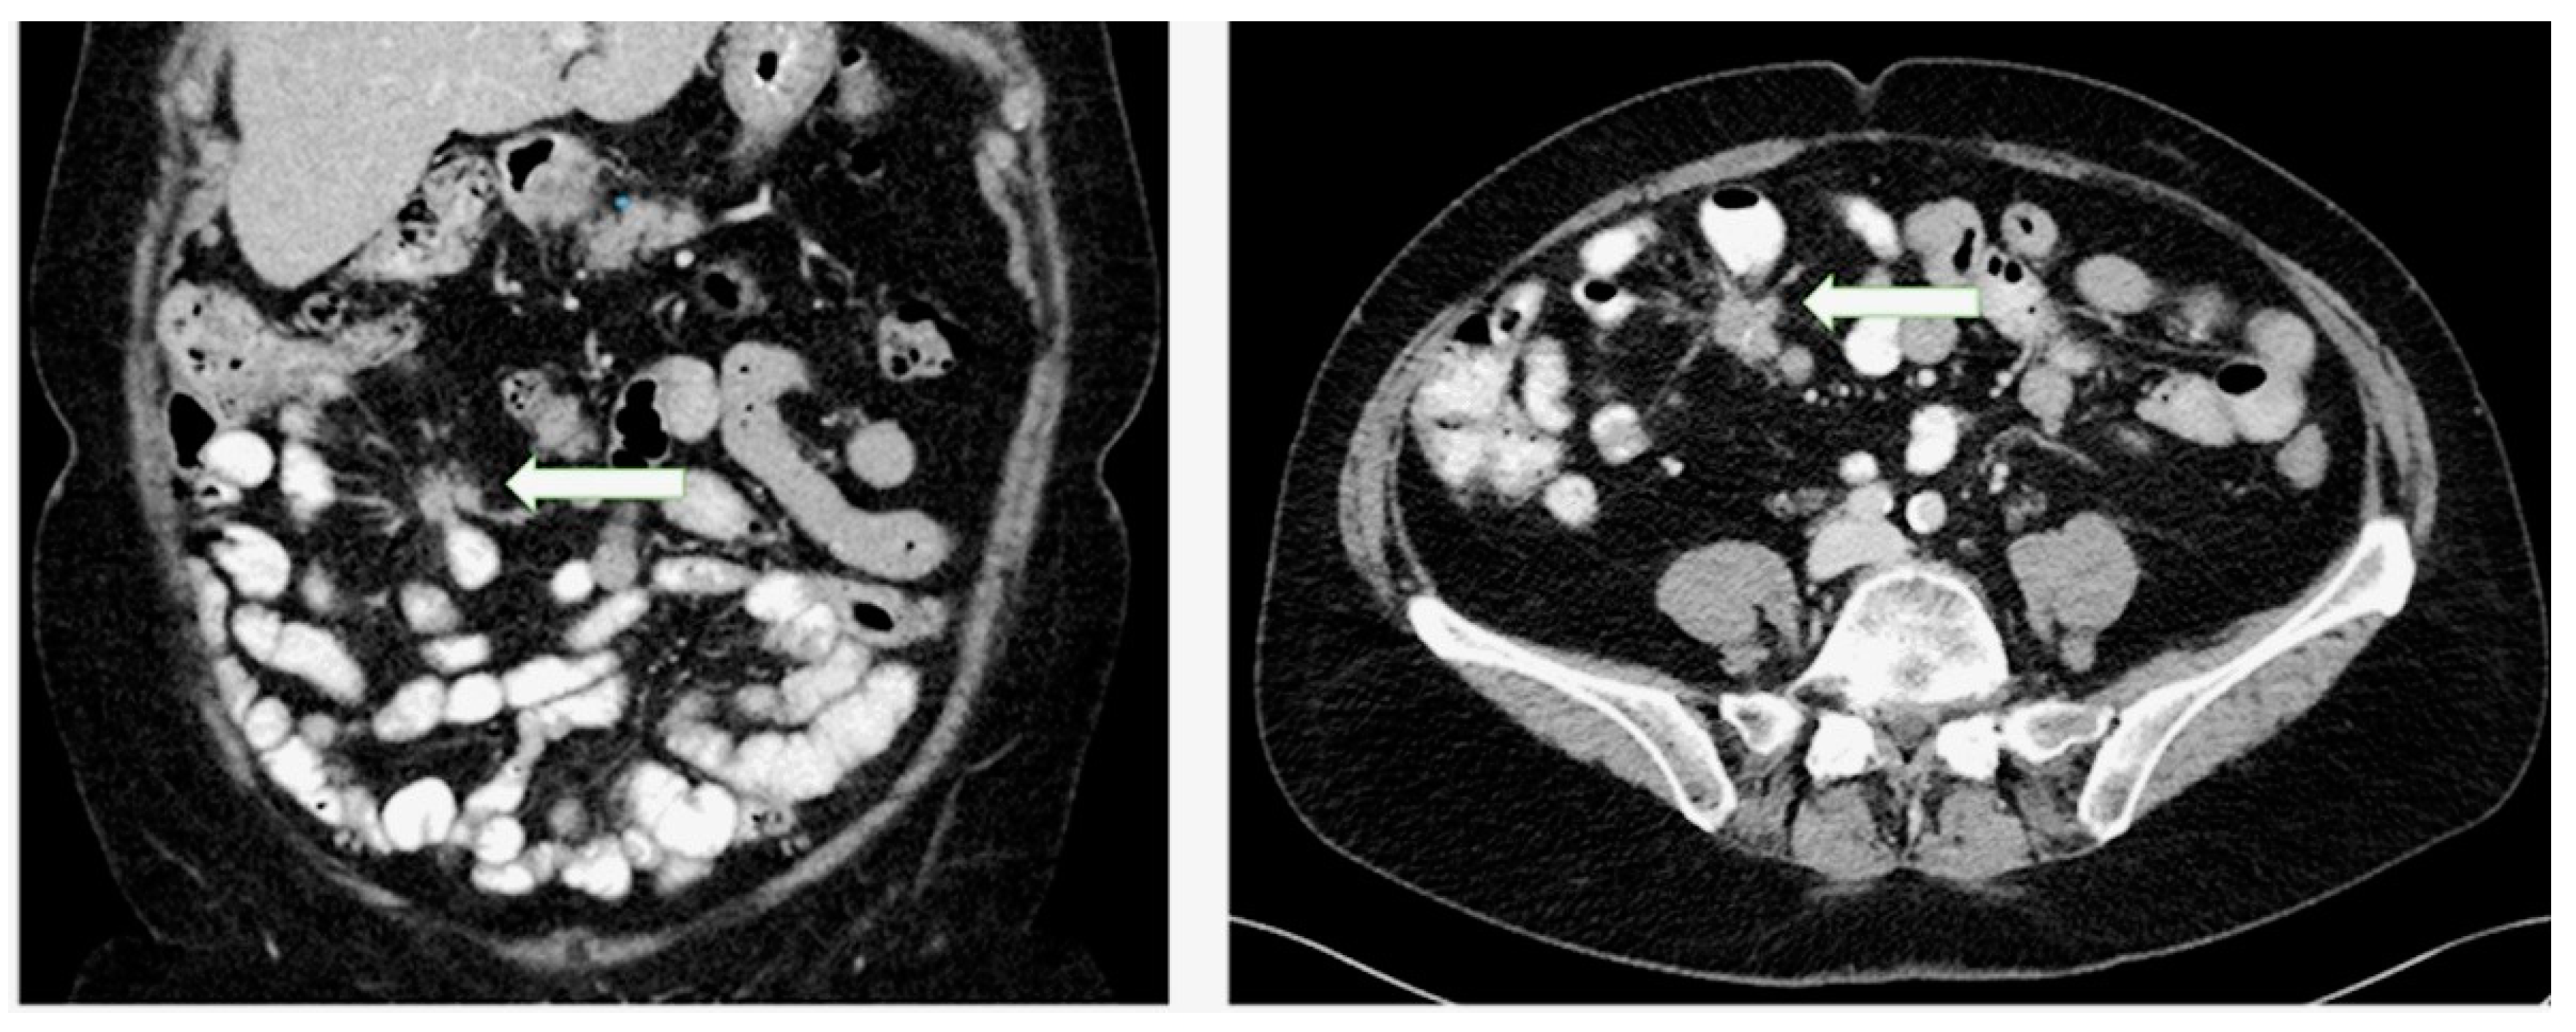

- Pantongrag-Brown, L.; Buetow, P.C.; Carr, N.J.; Lichtenstein, J.E.; Buck, J.L. Calcification and fibrosis in mesenteric carcinoid tumor: CT findings and pathologic correlation. AJR Am. J. Roentgenol. 1995, 164, 387–391. [Google Scholar] [CrossRef] [PubMed]

- Laskaratos, F.M.; Hall, A.; Alexander, S.; Stempel, C.V.; Bretherton, J.; Luong, T.V.; Watkins, J.; Ogunbiyi, O.; Toumpanakis, C.; Mandair, D.; et al. Is computed tomography an accurate diagnostic modality for the detection of mesenteric fibrosis in midgut neuroendocrine tumours? Gastroenterology 2019, 156, S-369. [Google Scholar] [CrossRef]

- Rodriguez Laval, V.; Pavel, M.; Steffen, I.G.; Baur, A.D.; Dilz, L.M.; Fischer, C.; Detjen, K.; Prasad, V.; Pascher, A.; Geisel, D.; et al. Mesenteric fibrosis in midgut neuroendocrine tumors: Functionality and radiological features. Neuroendocrinology 2018, 106, 139–147. [Google Scholar] [CrossRef] [PubMed]